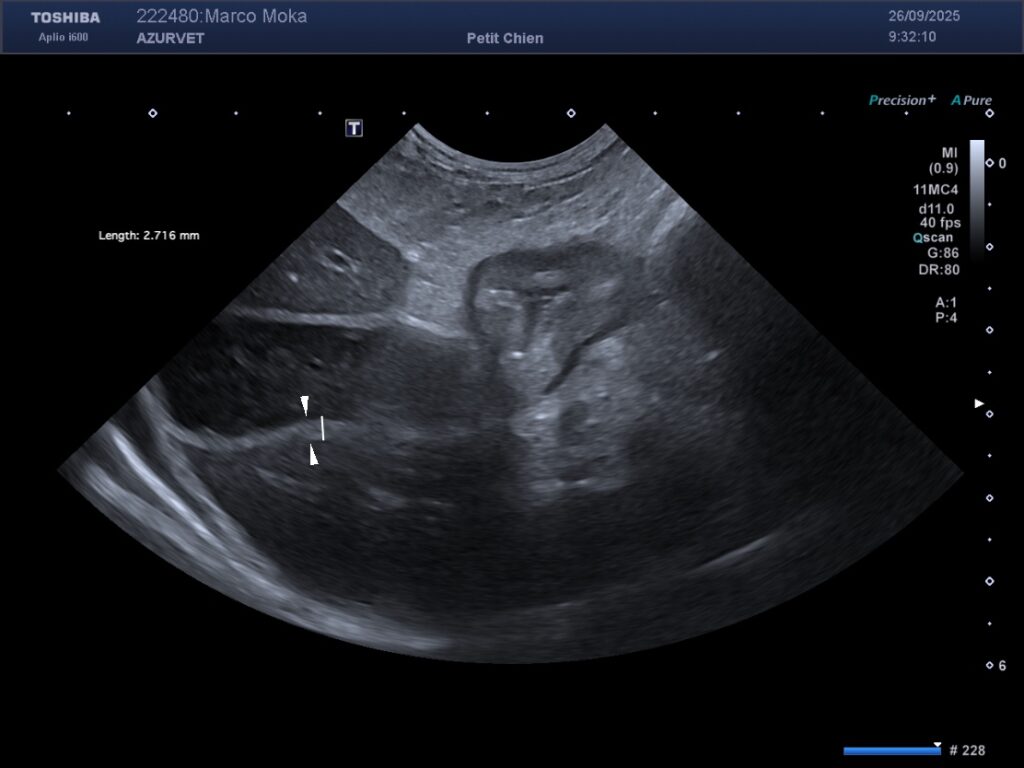

3) la recherche de thrombus artériel ou veineux (secondaire à la fuite de protéines anticoagulantes dans le tube digestif) : figure 4 et 5 ci dessous.

Figure 4 : thrombus dans l’artère iliaque externe G du Pinscher des figures 1 et 2. L’animal présentait une boiterie du membre pelvien G apparue de façon concomittabte aux troubles digestifs.